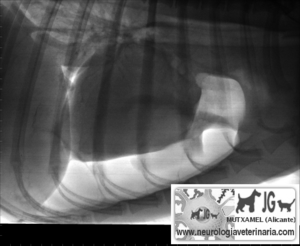

Neumotórax |